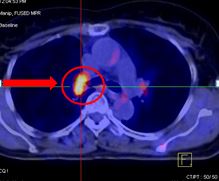

U phế quản gốc phải KT: 1,6x2,9cm, Max SUV=5,76 |

Tổn thương xương cánh chậu phải max SUV=5,34, Tổn thương S1,Max SUV=4,4 |

Chẩn đoán: K phổi di căn hạch trung thất di căn xương T4N2M1, giai đoạn IV